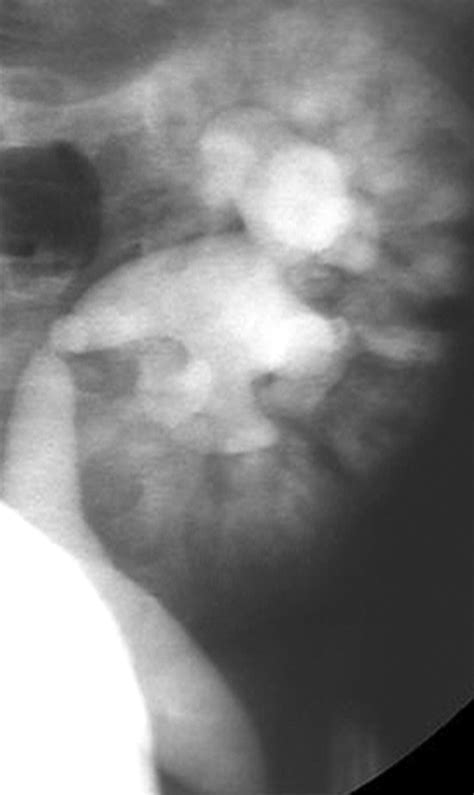

The Vcug medical abbreviation represents a diagnostic imaging test that focuses on the anatomy and function of the lower urinary tract. Unlike a standard ultrasound, which uses sound waves, a VCUG utilizes fluoroscopy—a continuous X-ray technique—to visualize the urinary tract in real-time as the bladder fills and empties. This procedure is most commonly performed on children to investigate recurrent urinary tract infections (UTIs) or to check for structural abnormalities.

The primary goal of this examination is to detect a condition known as vesicoureteral reflux (VUR), which occurs when urine flows backward from the bladder into the ureters and potentially back toward the kidneys. Left untreated, this backflow can lead to kidney scarring or long-term damage.

• Imaging: As the bladder fills and the patient is asked to urinate, the radiologist uses a fluoroscope to take real-time images. This allows the medical team to see if any liquid travels the wrong way toward the kidneys.